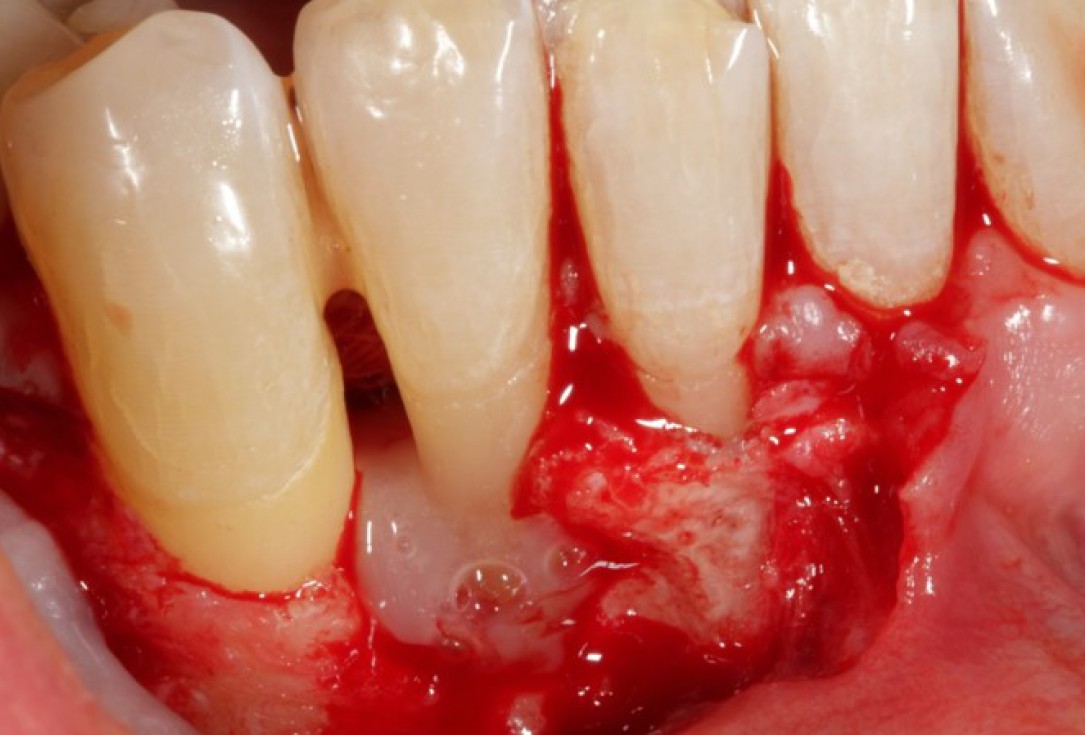

04/08 - Intra-operative view of the defect area.

Non-contained intrabony defect treated using Straumann® Emdogain® and a synthetic bone grafting material - Prof. Dr. Dr. A. Kasaj